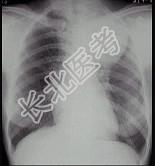

- 单项选择题女,25岁, 胸背痛2周,胸片如图, 最可能的诊断为 ( )

A、左上肺不张

B、左上肺炎

C、纵隔肿瘤

D、左上肺癌

E、左上肺炎性假瘤